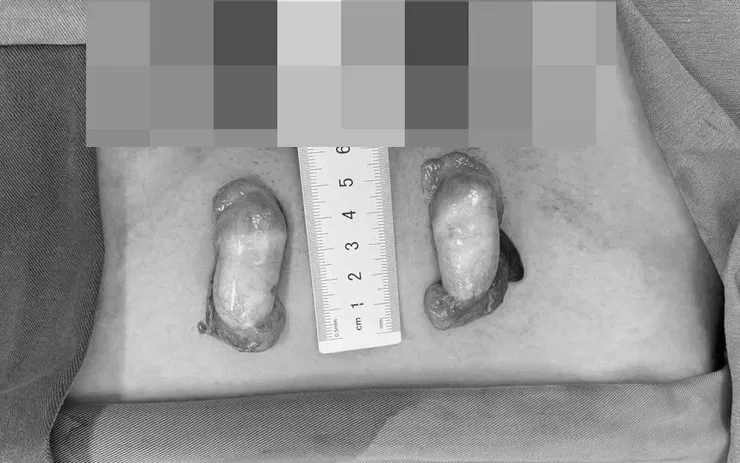

Tinh hoàn ẩn của bệnh nhân.

Khám lâm sàng cho thấy dương vật nhỏ, lỗ tiểu mở thấp ở tầng sinh môn và không sờ thấy tinh hoàn trong bìu. Kết quả xét nghiệm xác định bộ nhiễm sắc thể 46,XY - giới tính di truyền là nam, testosterone ở mức sinh lý nam giới. Chụp MRI phát hiện hai tinh hoàn nằm trong ống bẹn, không có tử cung và buồng trứng.

Các bác sĩ chẩn đoán người bệnh mắc rối loạn phát triển giới tính thể 46,XY - một dạng bất thường di truyền hiếm gặp (0,01–0,02%) khi kiểu gen, hormone và hình thể không thống nhất. Bệnh nhân được phẫu thuật hạ tinh hoàn hai bên xuống bìu và sinh thiết mô tinh hoàn để đánh giá chức năng sinh tinh.